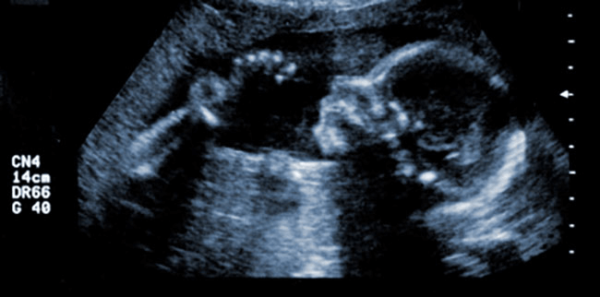

Νέα έρευνα δείχνει πιθανό κίνδυνο για ψυχική και σωματική βλάβη στις γυναίκες που υποβάλλονται κατόπιν επιλογής τους σε φαρμακευτική άμβλωση.

Μια πρόσφατα δημοσιευμένη έρευνα περιγράφει λεπτομερώς τον αυξημένο κίνδυνο να υπάρξουν ψυχολογικές και σωματικές συνέπειες στις γυναίκες που υποβάλλονται εκούσια σε φαρμακευτικές αποβολές. Οι ερευνητές, που συνέταξαν τη μελέτη, αναφέρουν λεπτομερώς τις σοβαρές αρνητικές συμπεριφορικές και τις φυσιολογικές επιδράσεις που παρατηρήθηκαν σε πειραματόζωα (αρουραίοι), τα οποία υποβλήθηκαν σε φαρμακευτική άμβλωση. Αυτή είναι η πρώτη έρευνα του είδους της, η οποία διερευνά τις βιολογικές και συμπεριφορικές συνέπειες της φαρμακευτικά επαγομένης άμβλωσης σε πειραματόζωα.